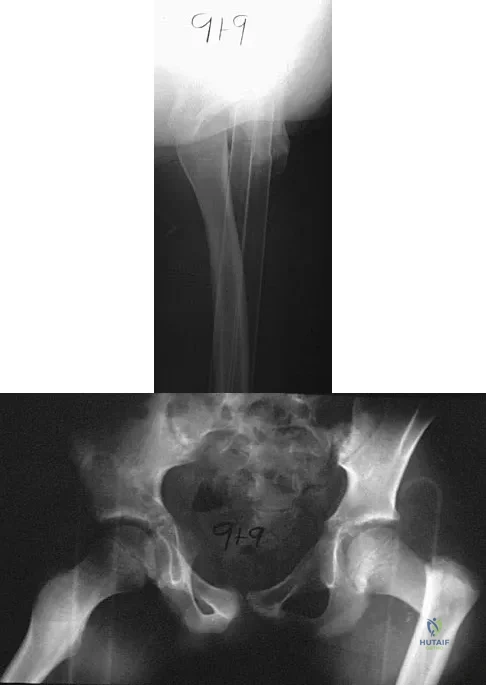

In 1980, a 32-year-old woman was found to have right breast mass, and a biopsy revealed adenocarcinoma. She underwent a mastectomy at that time, with no other treatment. Five years later, she noticed a lump in the left breast and underwent a left mastectomy. Seven lymph nodes were positive. In 2006, she now reports hip and thigh pain for the past 3 months. Figures 69a and 69b show AP and lateral radiographs of the femur. A bone scan shows a solitary lesion. Following radiographic staging, what is the next most appropriate step in management?

Explanation